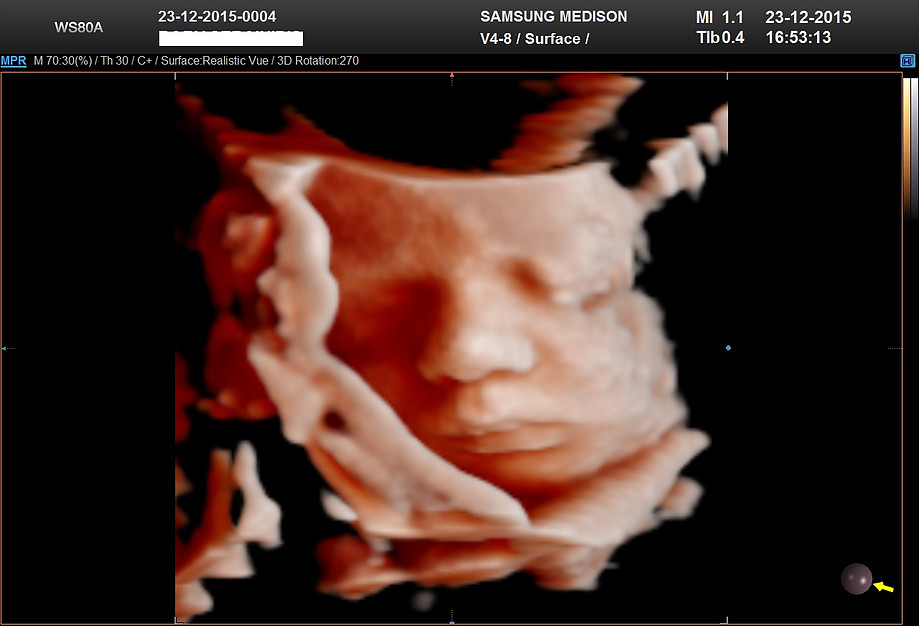

It excites them to see their unborn baby movements.

Ultrasound scans are the highlight of the pregnancy, it is taken at any intervals during the pregnancy period.

Moreover, it enables the mother to see the priceless view of their baby’s cutest reactions like yawning, smiling inside the womb.